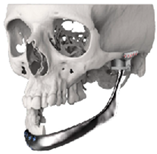

| ID | Age | eTMJR Class | Image | Reconstructed Structures | Fossa Materials | Condyle Materials | Screws and Fixation Holes |

|---|---|---|---|---|---|---|---|

| 1 | 71 | FT-M0 | ![]() | Temporal bone, aygomatic arch, glenoid fossa and condyle | Unalloyed titanium mesh temporal and zygomatic backing capping the UHMWPE fossa | Cobalt-chromiun-molybdenum alloy condylar head and Titanium alloy body | Skull component: 62.0 mm titanium screws. Manibular component: 82.7 mm titanium screws |

| 2 | 58 | FA-M0 | ![]() | Glenoid fossa with medial extension and condyle | Alloyed titanium backing capping the UHMWPE fossa | Cobalt-chromiun-molybdenum alloy condylar head and Titanium alloy body | Skull component: 52.0 mm titanium screws. Manibular component: 82.7 mm titanium screws |

| 3 | 41 | FO-M3 * | ![]() | Glenoid fossa and complete left hemimandible | Alloyed titanium backing capping the UHMWPE fossa | Cobalt-chromiun-molybdenum alloy condylar head and Titanium alloy body consisting of two interloching pieces | Skull component: 52.0 mm titanium screws. Manibular component: 112.7 mm titanium screws |

| 4 | 71 | FA-M3 | ![]() | Left zygomatic arch, glenoid fossa and complete left hemimandible extended to the right hemimandible ramus | Alloyed titanium zygomatic backing capping the UHMWPE fossa | Titantium alloy | Skull component: 82.3 mm titanium screws. Manibular component: 62.7 mm titanium screws |

| 5 | 26 | FA-M0 | ![]() | Temporal bone, zygomatic arch, glenoid fossa and condyle bilatreally | Alloyed titanium zygomatic backing capping the UHMWPE fossa | Cobalt-chromiun-molybdenum alloy condylar head and Titanium alloy body | Skull component: 172.0 mm titanium screws. Manibular component: 192.7 mm titanium screws |

| 6 | 54 | F0-M2 | ![]() | Glenoid fossa and complete right hemimandible | Alloyed titanium backing capping the UHMWPE fossa | Cobalt-chromiun-molybdenum alloy condylar head and Titanium alloy mesh body | Skull component: 52.3 mm titanium screws. Manibular component: 92.7 mm titanium screws |

| 7 | 63 | F0-M3 | ![]() | Glenoid fossa and complete left hemimandible | Alloyed titanium backing capping the UHMWPE fossa | Cobalt-chromiun-molybdenum alloy | Skull component: 52.3 mm titanium screws. Manibular component: 82.7 mm titanium screws |

| 8 | 24 | F0-M3 * | ![]() | Glenoid fossa and complete right hemimandible extended to the left hemimandible ramus | Cobalt-chromium-molybdenum alloy backing capping the UHMWPE fossa | Cobalt-chromiun-molybdenum alloy | Skull component: 52.3 mm titanium screws. Manibular component: 112.7 mm titanium screws |

| 9 | 52 | FT-M0 | ![]() | Temporal bone, zygomatic arch, glenoid fossa extended medially and condyle | Cobalt-chromium-molybdenum alloy backing capping the UHMWPE fossa | Cobalt-chromiun-molybdenum alloy | Skull component: 82.3 mm titanium screws. Manibular component: 82.7 mm titanium screws |